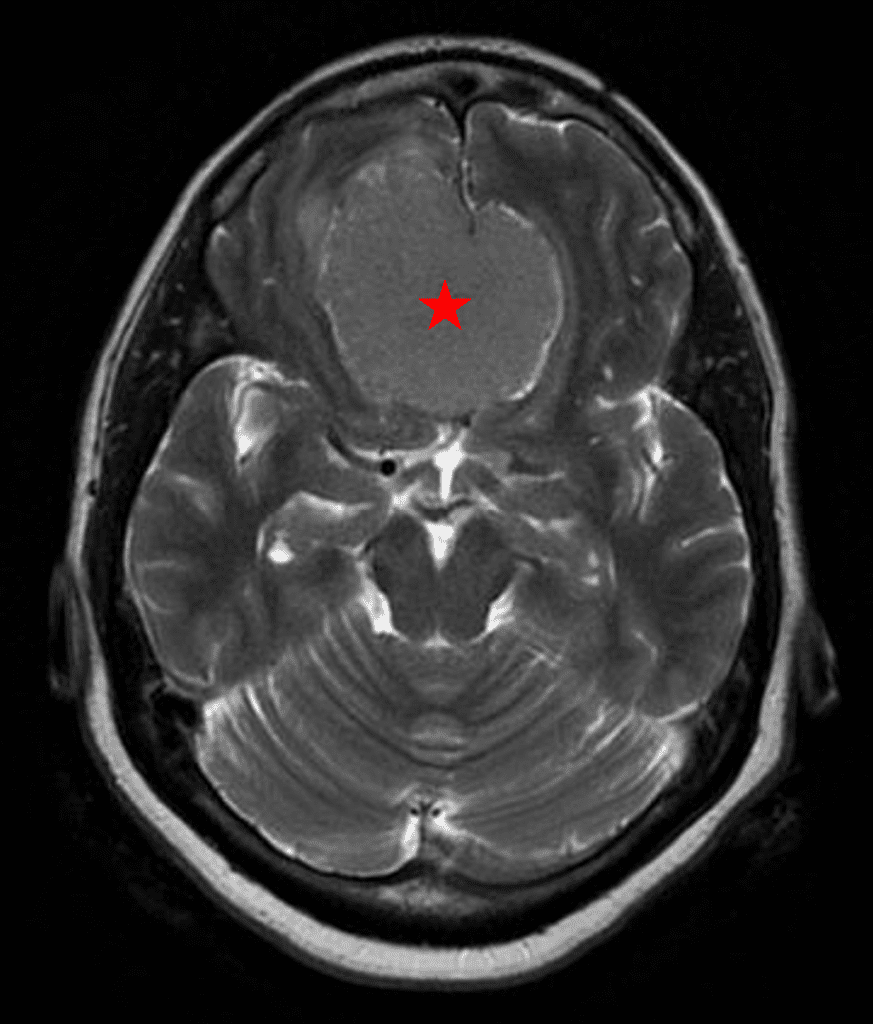

This is a 49-year-old otherwise healthy female who presented with bifrontal and retro-orbital headaches, behavioral changes, and forgetfulness. Symptoms have been progressively worsening over the past month. Her neurologic exam revealed a pronator drift, otherwise was unremarkable. MRI brain demonstrated a large extra-axial homogeneously enhancing mass of the anterior cranial fossa, resulting in significant mass effect and vasogenic edema (Figure 1a and 2a). Imaging was most consistent with a planum sphenoidale meningioma. She was referred to Dr. Xavier Gaudin for neurosurgical evaluation.

Figure 1a – Preoperative MRI demonstrating an extra-axial enhancing mass of the anterior cranial fossa.